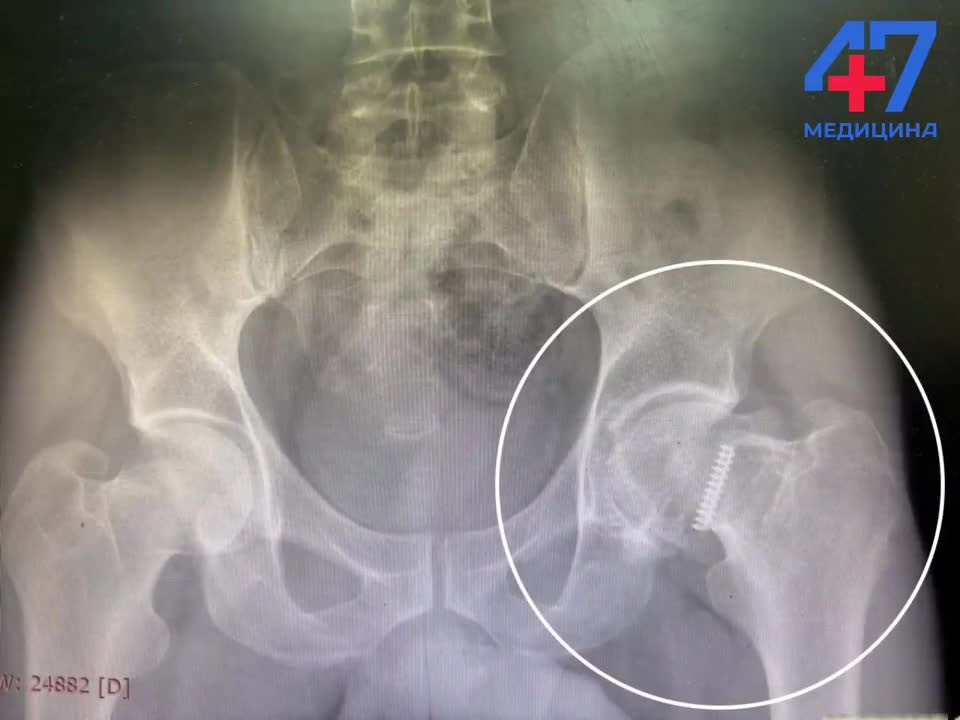

В Выборгской больнице выполнили сложное эндопротезирование тазобедренного сустава. Пациентом стал житель Енакиево (ДНР), у которого из-за обломка болта в костной ткани развился посттравматический коксартроз. Как объяснили в пресс-службе регионального комитета по здравоохранению, 20 лет назад мужчина получил перелом шейки бедра и ему провели операцию остеосинтеза, для фиксации кости установили три металлических болта. Позже конструкцию удалили, но один болт сломался при извлечении и его фрагмент остался в костной ткани. Обломок привел к постепенному разрушению тазобедренного сустава. 6 октября мужчину приняли в травматологическом отделении Выборгской больницы. Обследование позволило установить точное расположение болта, его отношение к сосудам и нервам. Единственным эффективным методом лечения стала замена сустава на искусственный. Операцию выполнили в два этапа - сначала извлекли обломок болта, а после установили эндопротез тазобедренного сустава.

В Выборгской больнице выполнили сложное эндопротезирование тазобедренного сустава. Пациентом стал житель Енакиево (ДНР), у которого из-за обломка болта в костной ткани развился посттравматический коксартроз.

Как объяснили в пресс-службе регионального комитета по здравоохранению, 20 лет назад мужчина получил перелом шейки бедра и ему провели операцию остеосинтеза, для фиксации кости установили три металлических болта. Позже конструкцию удалили, но один болт сломался при извлечении и его фрагмент остался в костной ткани. Обломок привел к постепенному разрушению тазобедренного сустава.

6 октября мужчину приняли в травматологическом отделении Выборгской больницы. Обследование позволило установить точное расположение болта, его отношение к сосудам и нервам. Единственным эффективным методом лечения стала замена сустава на искусственный. Операцию выполнили в два этапа - сначала извлекли обломок болта, а после установили эндопротез тазобедренного сустава.